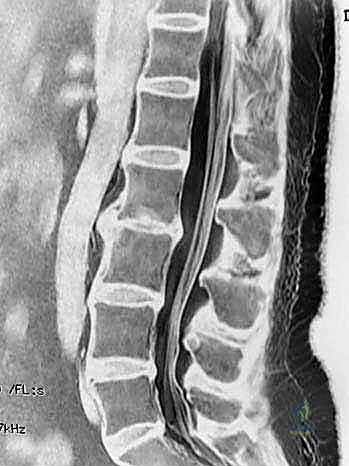

- التصوير بالرنين المغناطيسي (MRI): المعيار الذهبي لتقييم الأنسجة الرخوة. يوضح بدقة حالة الأقراص الفقرية، ودرجة جفافها، ومقدار الضغط على الحبل الشوكي وجذور الأعصاب.

- التصوير المقطعي المحوسب (CT Scan): يقدم تفاصيل دقيقة للغاية عن البنية العظمية، وهو ضروري جداً للتخطيط الجراحي، خاصة في حالات استئصال الجسم الفقري أو وجود تعظم شديد.